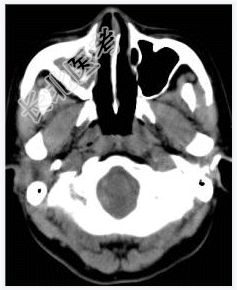

- [材料题] 女性,50岁。鼻塞2年余,有异物感,有血性分泌物,伴面颊疼痛。行CT检查。

- 简答题1、患者的诊断及依据是什么?

- 简答题2、需要与哪些疾病鉴别?